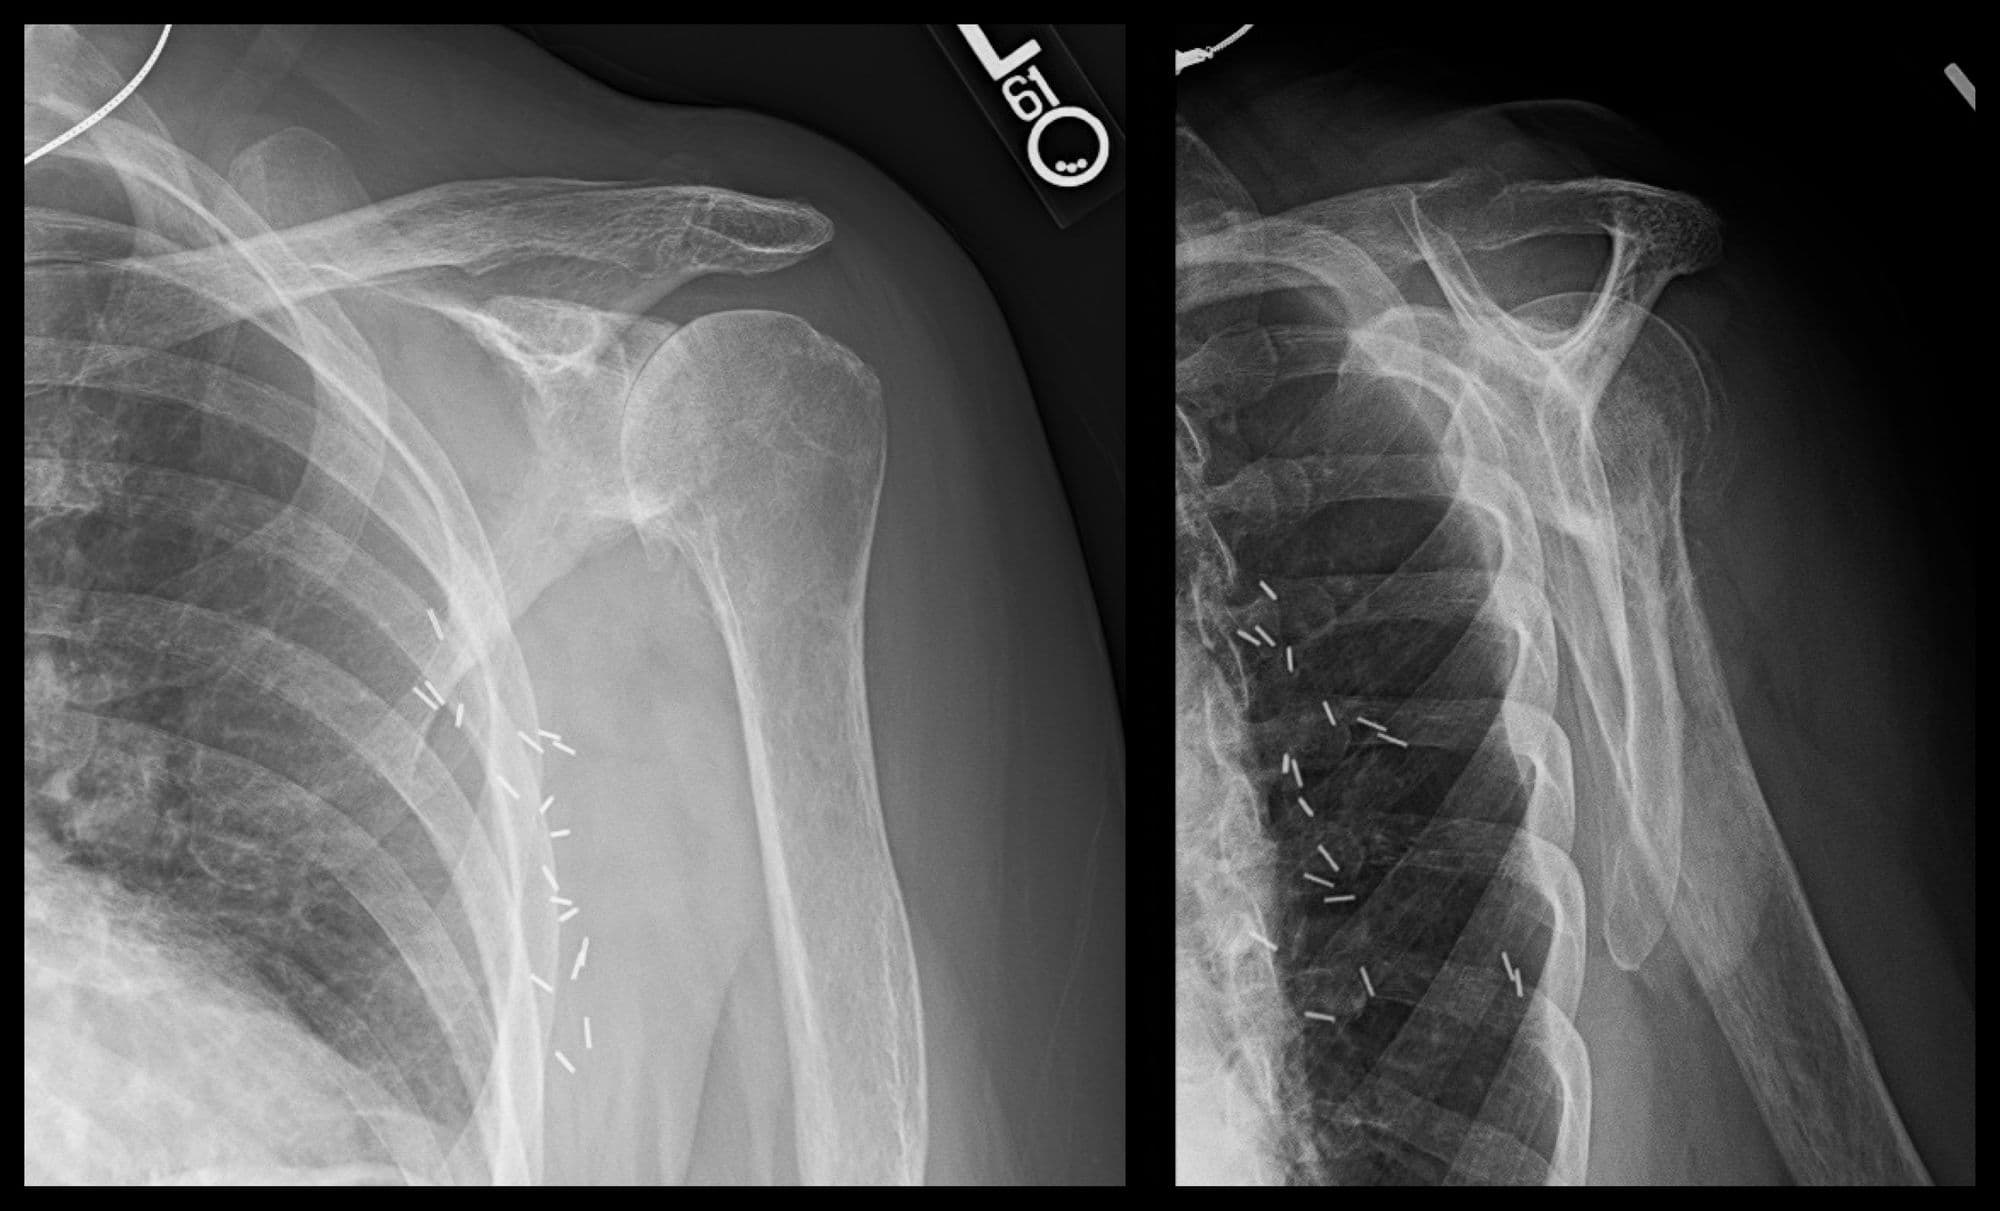

Reverse Shoulder Arthroplasty (patient-specific guide)

Sports

Anatomic Total Shoulder Arthroplasty

Reverse Shoulder Arthroplasty